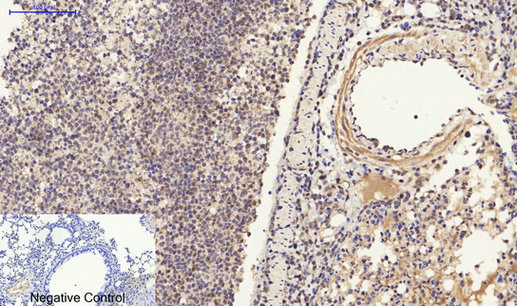

Immunohistochemistry analysis of paraffin-embedded mouse lung tissue using ERβ antibody.High-pressure and temperature Sodium Citrate pH 6.0 was used for antigen retrieval. Negative control was used by secondary antibody only.